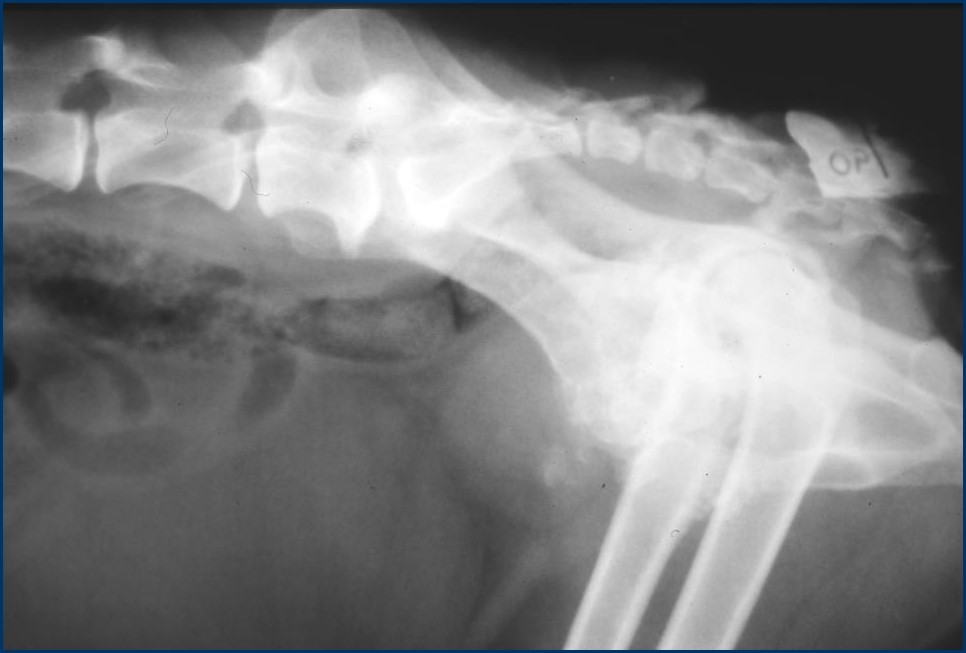

What can be seen here?

Mineral and irregular prostate

New bone around pelvis

Spondylosis of L vert

Which prostatic conditions may be associated with intra prostatic mineralisation? (2)

–Chronic prostatitis

– Neoplasia

New bone on the ventral aspect of caudal vertebrae

Spondylosis

Between end plates – more irregular aggressive new bone

If you get this on caudal vert – pathognomic of neoplasia mets

Marked ST opacity ventralll – LN (infection, or neoplasia)